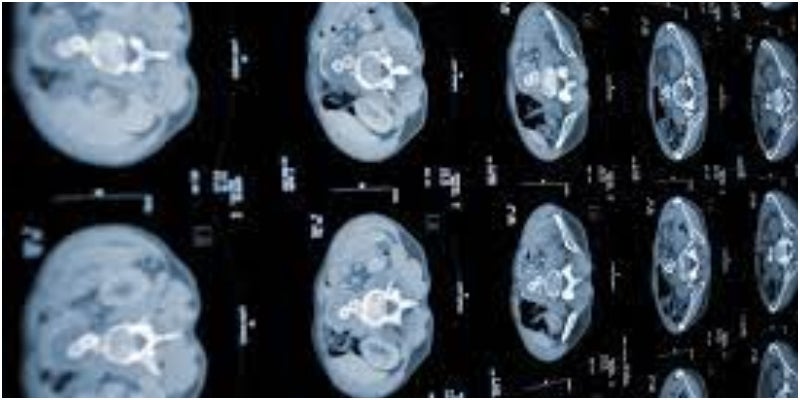

La inteligencia artificial (IA) podría desempeñar un papel crucial en la prevención y detección del cáncer de páncreas, así como en los tumores cancerígenos derivados de la presencia de la enfermedad. Su aplicación en la detección de diversos tipos de cánceres se vislumbra como un respaldo en los estudios actuales con tomografías computarizadas (TC), generando modelos e imágenes 2D y 3D mediante la computadora.

Con la asistencia de esta tecnología, las TC podrían identificar los tumores pequeños, un desafío en la prevención oportuna del cáncer de páncreas para los expertos. Ya que uno de los principales obstáculos en este proceso es la falta de síntomas en las primeras etapas de la enfermedad, hasta que se propaga hacia otros órganos, según la Mayo Clinic.

Las imágenes de IA detectan el cáncer de páncreas

Un estudio reciente reveló la eficacia de una herramienta de inteligencia artificial de detección asistida por computadora (CAD). La IA logró una sensibilidad del 89,9% y una especificidad del 95,9% en la identificación de tumores.

En particular, la sensibilidad para detectar tumores de menos de dos centímetros fue del 74,7%. Esto reduce el tiempo de espera para recibir atención temprana del cáncer de páncreas en etapas iniciales, según las conclusiones del estudio publicado en la revista BMC Cancer.